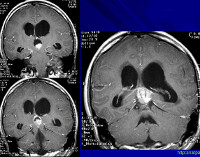

• Нейровизуализацию. Предпочтение отдаётся МРТ головного мозга, в старшем возрасте при наличии противопоказаний к МРТ возможно проведение церебральной КТ. Нейровизуализирующие методики дают возможность диагностировать неоплазию, определить характер её роста, установить локализацию и распространённость процесса.